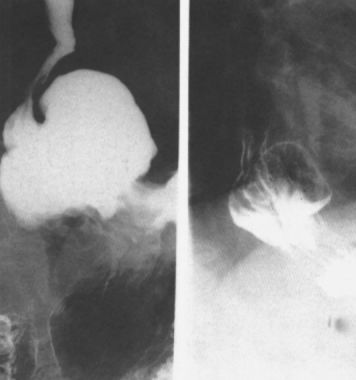

食管静脉曲张:蚯蚓样、串珠状。

食管重度静脉曲张

食管静脉曲张:食管黏膜呈现蚯蚓状

这是食管静脉曲张伴胃底静脉曲张的图像